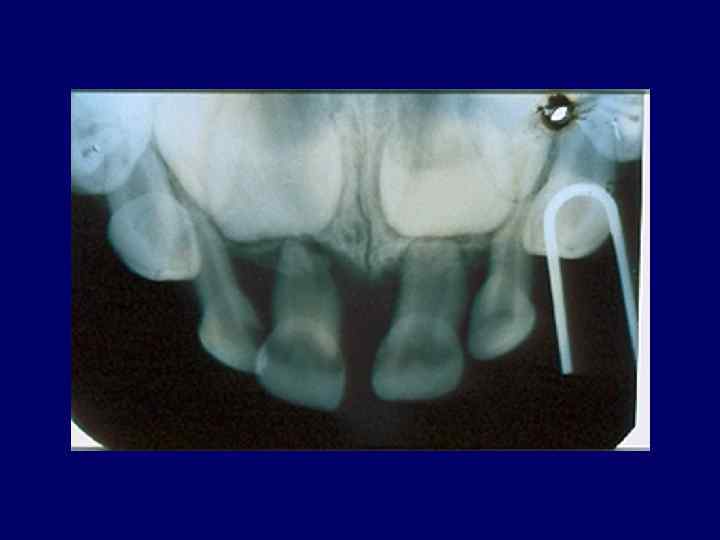

• 1, 5– 2 есеге иммунорегуляторлы индекстің тұрақты төмендеуі (Т-лимфоциттердің хелперлік және супрессорлық популяцияларының арақатынастарының бұзылуы), нәтижесінде пародонт қабынуының бұл түрінде ем нәтижесіз болады. • рентгенологиялық зерттеулерде (ортопантомография) қабынулы деструктивті процесстің белсенділігін көрсететін альвеолярлы өсіндінің сүйек тінінің жайылмалы бұзылысы шекарасы анық емес остеопороздың ірі ошақтарын